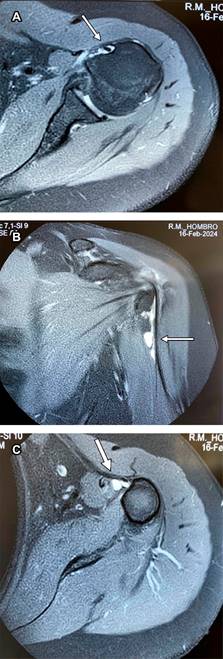

Se trata de paciente femenino de 69 con dolor en el hombro izquierdo de seis meses de evolución, principalmente con movimientos de abducción y flexión de codo. A la exploración de hombro izquierdo: arcos de movimiento limitados en abducción a 90o por dolor al igual que rotación externa de 45o, a la palpación masa dolorosa de aproximadamente 2 cm en borde interno del tendón de la porción larga del bíceps por debajo de la corredera bicipital. Prueba de choque de Neer, Hawkins y prueba de Yergason positivas; pruebas de inestabilidad de la articulación glenohumeral negativas. Las radiografías simples no mostraron hallazgos anormales. La resonancia magnética mostró: tendinosis del supraespinoso con ruptura parcial en su inserción, además de acromion tipo III con osteofitos subacromiales causantes de pinzamiento (Figura 1); en ponderación T2 se encontró tendinopatía de la porción larga del bíceps braquial con incremento de líquido en la corredera bicipital y quiste sinovial en su tercio proximal de 2.0 × 1.4 × 1.2 cm, con apariencia de estar encapsulada por la vaina del tendón bicipital (Figuras 2 y 3). Se canalizó a cirugía articular.

Figura 2: Imagen de resonancia magnética del hombro izquierdo, ponderada en T2 en corte coronal. Se observa quiste ganglionar en el tendón largo del bíceps, por debajo de la corredera bicipital (flecha) con dimensiones de 2.0 × 1.4 × 1.2 cm y abundante líquido en la vaina tendinosa (flechas punteadas).

Figura 3: Imágenes de resonancia magnética de hombro izquierdo. A) Corte axial a nivel de corredera bicipital que muestra tendinopatía crónica. B) Corte coronal, se observa quiste por debajo de la corredera bicipital. C) Corte axial, muestra el inicio del quiste ganglionar (flechas).